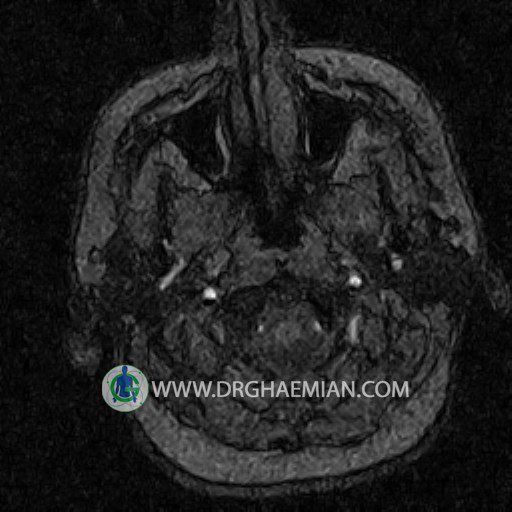

CRANIAL MRV

Technique: TOF ( time of flight ).

Images of the venous cranial vessels demonstrates a superior sagittal sinus of normal caliber with normal arrangement of draining superficial cerebral veins.

The great cerebral vein Galen inferior sagittal , straight sinus and left sigmoid sinuses appear normal.

The right transverse and sigmoid sinuses present a normal caliber.

The other evaluable deep cerebral veins , basal and labbe are normally developed and patent.

– Narrowing of left transverse sinus without inthimal irregularity & without filling defect suggestive for cengenital hypoplasia

– Two high signal focus ( 9 mm & 11 mm in diameter ) in left internal capsule suggestive for ischemic foci & low grade glioma

are seen